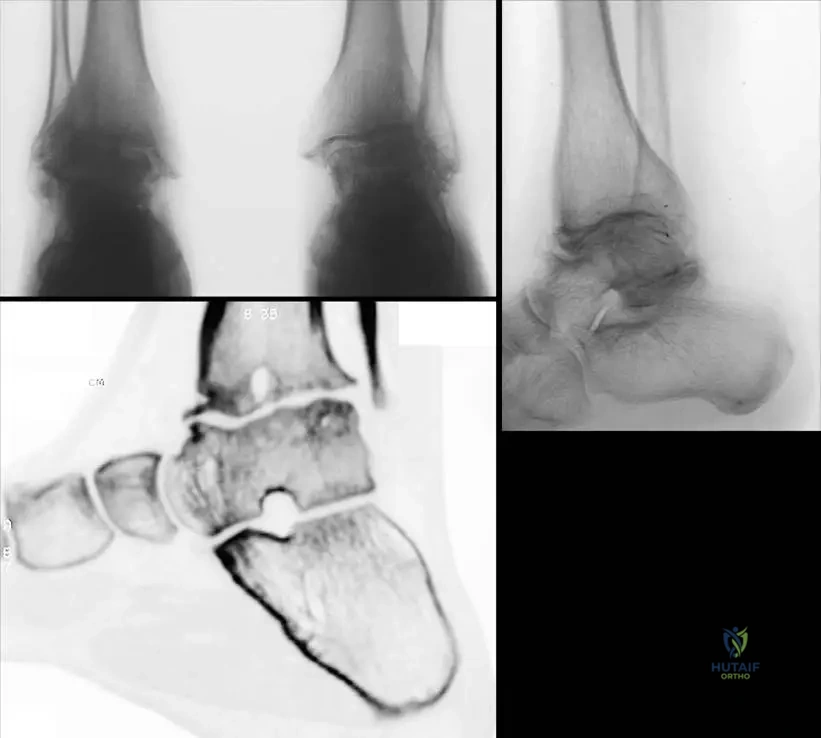

A 60-year-old man with a history of diabetes mellitus presents with a swollen, deformed, and insensate right ankle. He denies any significant trauma. Physical examination reveals a warm, erythematous, and unstable ankle joint with palpable crepitus. Radiographs show severe disorganization of the ankle joint, fragmentation of the talus, and extensive new bone formation.

View Answer & Explanation

Correct Answer: D

Rationale: The combination of a deformed, swollen, unstable, and insensate joint in a patient with diabetes, along with radiographic evidence of severe joint disorganization and new bone formation, is characteristic of Neurogenic Osteoarthropathy, also known as Charcot’s Joint. Diabetes is a common cause. Gout and bacterial arthritis are typically acute and painful. Osteoarthritis is a degenerative process, usually less destructive and not insensate. Reflex sympathetic dystrophy involves pain and autonomic dysfunction, not primary joint destruction.